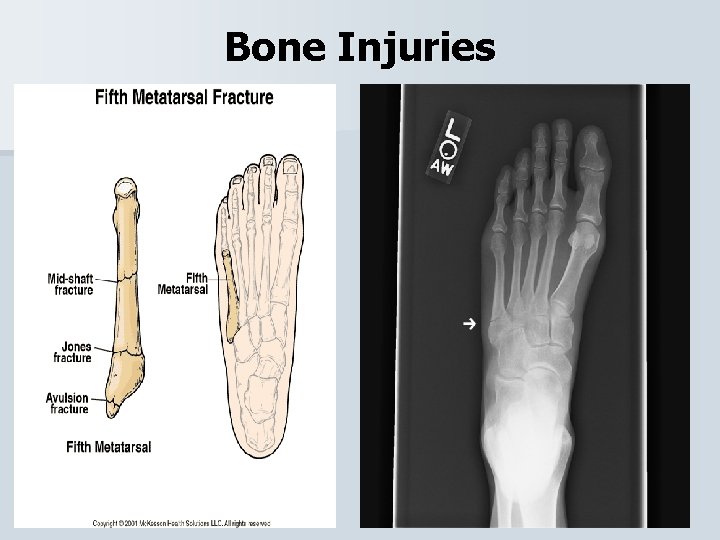

Bone Injuries

Bone Injuries Jones Fx • The most common avulsion fracture is of the 5 th metatarsal. • When the ankle is forced into inversion, the muscle contracts forcefully to stabilize the ankle and the peroneus brevis tendon pulls part of the bone away. • Refer

Bone Injuries